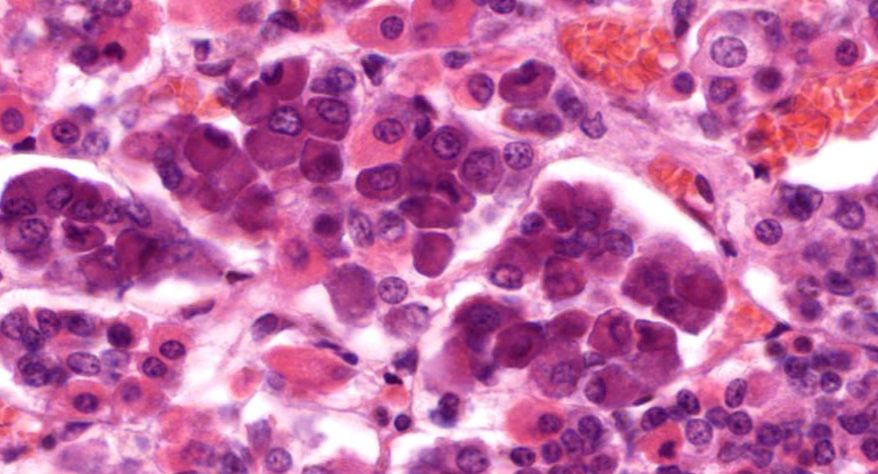

低倍镜观察:1. 被膜:由薄层结缔组织组成。2. 实质:由许多大小不等的滤泡构成。滤泡壁是单层立方上皮细胞,滤泡腔内充满粉红色匀质胶状物,滤泡之间的结缔组织内有丰富的血管。高倍镜观察:1. 滤泡:滤泡壁的单层滤泡上皮细胞一般呈低柱状或立方状,胞质着浅色,细胞核呈圆形。滤泡腔内充满了粉红色匀质胶质。2. 滤泡旁细胞:体积较大,呈圆形或椭圆形;细胞核较大,呈圆形,着色较浅,细胞质染色也较浅。细胞或嵌在滤泡壁上或成团分布于滤泡之间。3. 间质:由结缔组织组成。位于滤泡之间。其中含有丰富的毛细血管及三五成群的滤泡旁细胞。

5.滤泡旁细胞1

7.滤泡旁细胞2